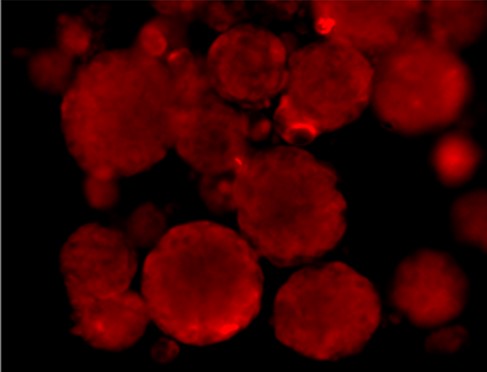

Immunofluorescence staining of Src and Phospho-Src

SRC total

P-SRC Tyr416